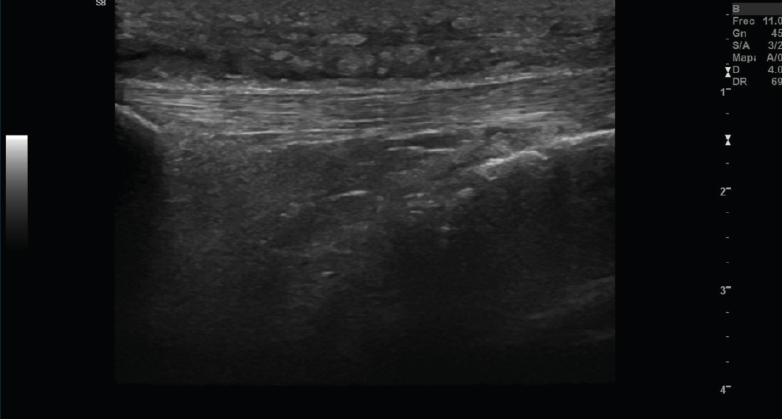

2.1. Tendinitis

Con ecografía Doppler pueden aparecer áreas de hiperemia intratendinosa o peritendinosa (Figura 8).

Figura 8. Corte sagital de una ecografía de rodilla del tendón rotuliano: engrosamiento del tendón con aumento difuso de ecogenicidad.